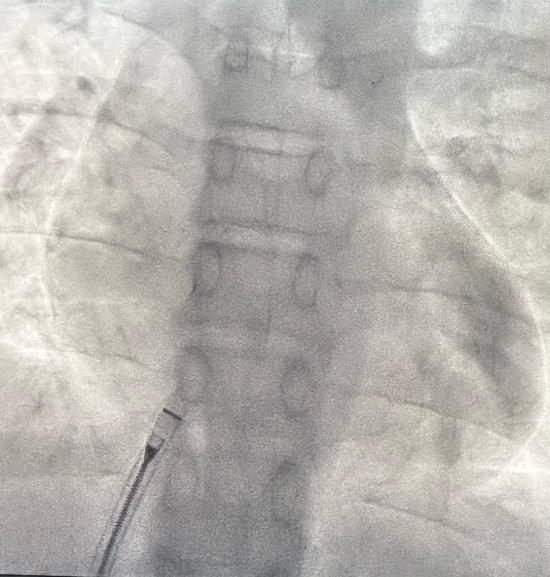

术后X线下无金属植入物

手术过程:精准微创,30分钟完成“补心”

手术在局部麻醉下进行,通过股静脉穿刺建立介入通道,在超声及X线引导下,将可降解封堵器精准输送至房间隔缺损处。封堵器展开后完全覆盖缺损部位,即刻超声显示分流消失,三尖瓣反流显著减少,手术全程耗时约1小时。术后患儿生命体征平稳,无不适症状,次日即可下床活动。其家属对治疗效果表示高度认可:“孩子终于能像其他同龄人一样正常上学,上体育课了,感谢宋主任团队!”